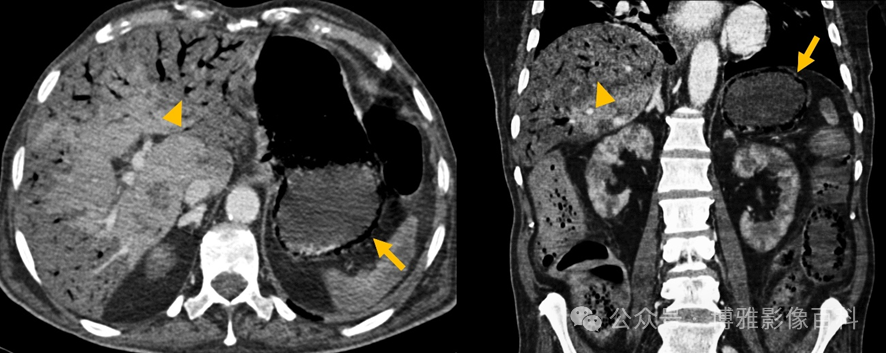

肝血管形成:门静脉(75%的血流,50%的含氧血),肝动脉(25%的血流,50%的含氧血)。

肝缺血:不常见的原因是:双重血管供应,经常存在依赖于胃左动脉和肠系膜上动脉的副动脉循环(第三供应)。

原因:医源性(介入手术、手术)、外伤、移植后、高凝状态、血管炎或感染(感染性休克)

影像表现:节段性分布的灌注缺损,定位于:外围:楔形(箭头)

1158ec61701c046f759c3f2eaf921fdd.png

图3:CT门静脉期。Whipple手术后患者中央:椭圆形/圆形(箭头)或不规则的管状形状,平行于胆管

f1ba046e851eef7b6c012cb252944bb5.png

图4:CT门静脉期。因急性肠系膜缺血而进行肠切除术。梗死更常发生在肝右叶,尽管原因不明。我们可以区分缺血(动脉期无强化,但门脉期等强化)和梗死(所有期相均无强化)。由于保留了未移位的门静脉束,它们可能有斑片状和不均匀的强化。这使得它能够与其他低增强病变(脓肿、胆汁瘤、血肿等)相鉴别。其轮廓是由病变时间决定的。在急性梗死中,边界更模糊,而在亚急性/慢性梗死中,边界更清晰。在无菌性和感染性梗死中都可能气体形成。无菌坏死气体继发于组织坏死。在特定的临床背景下,医生可能会怀疑存在继发感染。

后遗症:胆囊囊肿或胆囊湖:胆管上皮坏死导致胆汁外渗,最终被纤维组织(胆汁瘤)包围,形成肝内胆管局灶性扩张胆道狭窄胆囊回缩